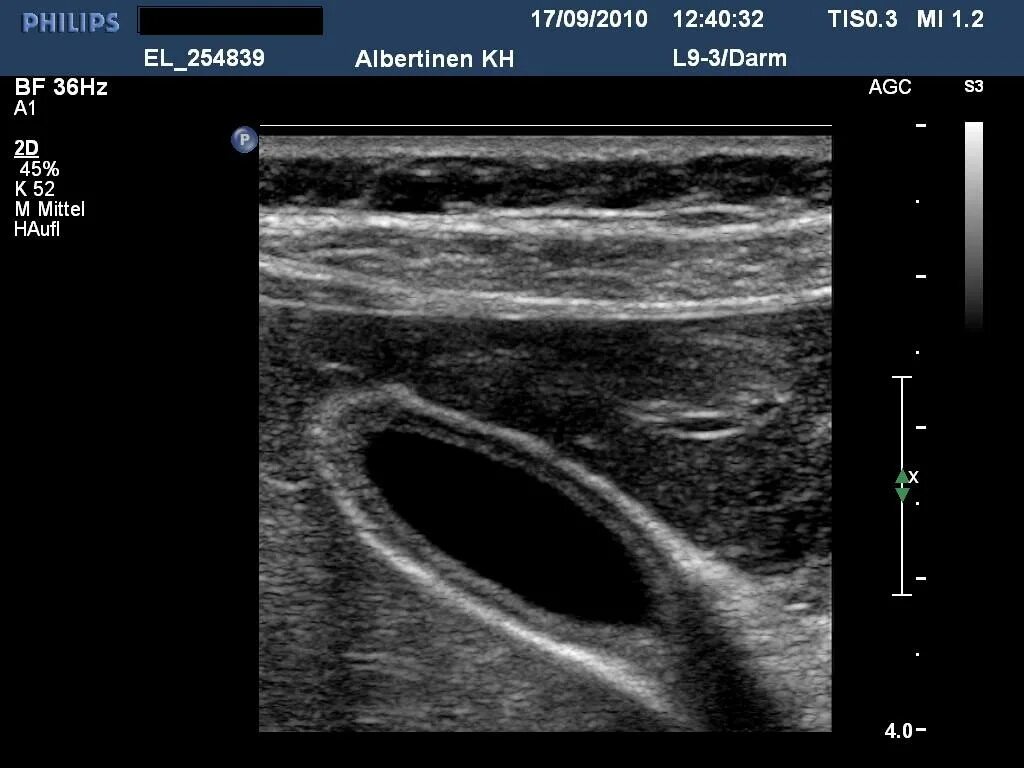

Узи желчного пузыря подготовка к процедуре